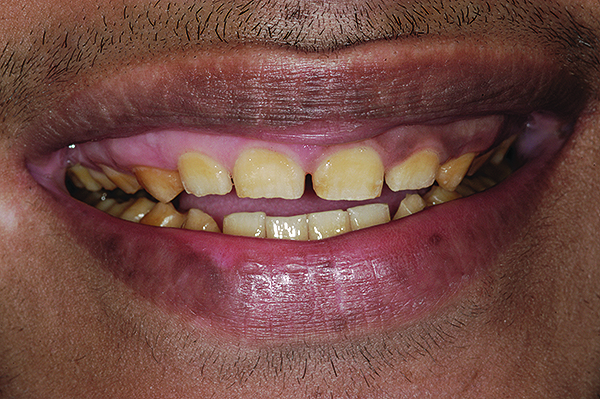

Figure 2. Preoperative 1:2 retracted frontal view.

Figure 2

A thorough clinical examination and analysis were carried out to assess the esthetic and functional problems of the patient (Figure 2 through Figure 7). The medical history was non-contributory, except for mild leukoderma. Temporomandibular joint (TMJ) function was within normal range.

Mounted study casts were used to evaluate occlusion. The relevant findings were as follows2: Facial analysis revealed a canted maxillary occlusal plane and canted dental midline. Dentolabial analysis showed that the maxillary incisors were not adequately visible during repose; it also revealed a reverse smile line, as well as a wide smile showing 12 teeth. Results from the phonetic analysis were that “F” and “V” sounds revealed upper incisal shortening, “M” and “S” pronunciation disclosed a diminished vertical dimension of occlusion (VDO), and “E” sounds showed severe shortening of incisors. Dental analysis revealed thick biotype, asymmetry and inappropriate location of gingival levels and zenith, incorrect axial inclinations, a displeasing width-to-length ratio, and pitted surfaces on most teeth. Interproximal decay was evident on several posterior teeth, as revealed by radiographic analysis. Finally, occlusal examination indicated discrepancy between maximum intercuspation (MIP) and centric relation (CR) as well as a lack of anterior guidance/posterior disclusion.